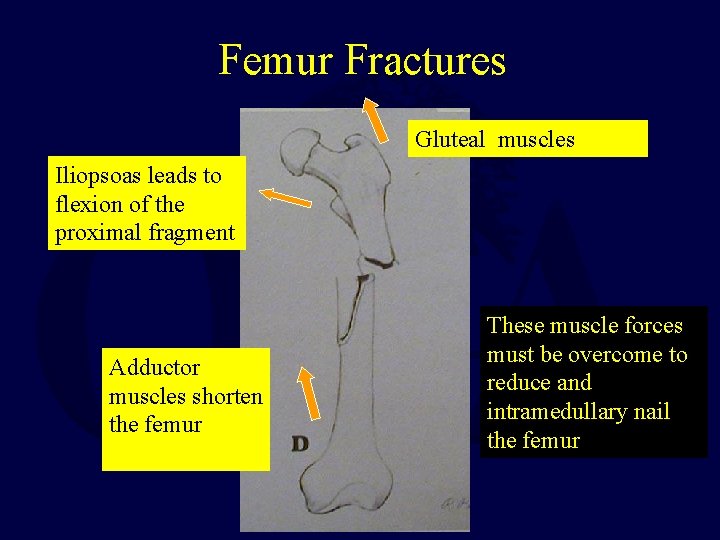

Femur Fractures Gluteal muscles Iliopsoas leads to flexion of the proximal fragment Adductor muscles shorten the femur These muscle forces must be overcome to reduce and intramedullary nail the femur